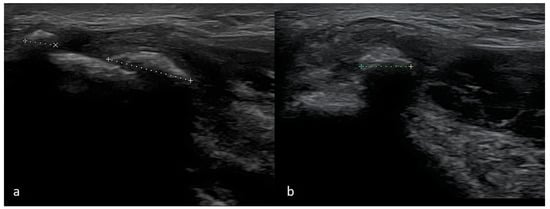

4.4. Ulnar Collateral Ligament Injury